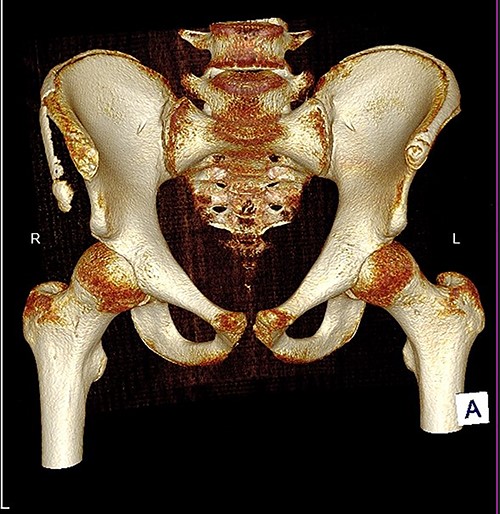

The anterior–posterior plain film X-Ray of pelvis demonstrated an avulsion fracture of the right ASIS and IC apophysis with 1.5 cm displacement (Fig. 1). Lateral view of the hip showed no extension into the joint. There was no radiological evidence of chronic overuse or previous injury. Computed tomography (CT) imaging was performed to better identify the injury; 3D volume reconstruction clearly demonstrated the unique fracture pattern of an ASIS avulsion in addition to an avulsion of the distal iliac apophysis extending ~5 cm with the described displacement (Figs 2–4).

3D reconstruction of tomographic CT scan illustrating avulsion fracture of ASIS and IC apophysis with its latero-inferior displacement (R - Right, L - Left, A - Anterior).